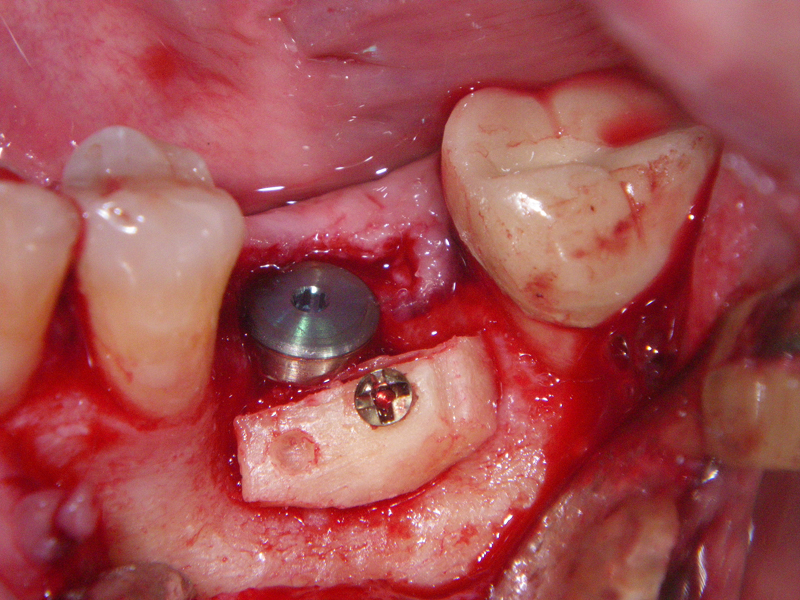

- Stage I: Implant placement/Sealing Screw

- Stage II: Implant uncovered healing cap

- Alveolar Ridge Augmentation

- Bone grafting – autogeneous, alogenic, xenogenic

- Blockgraft

- Fixation (plate, screws, wire)